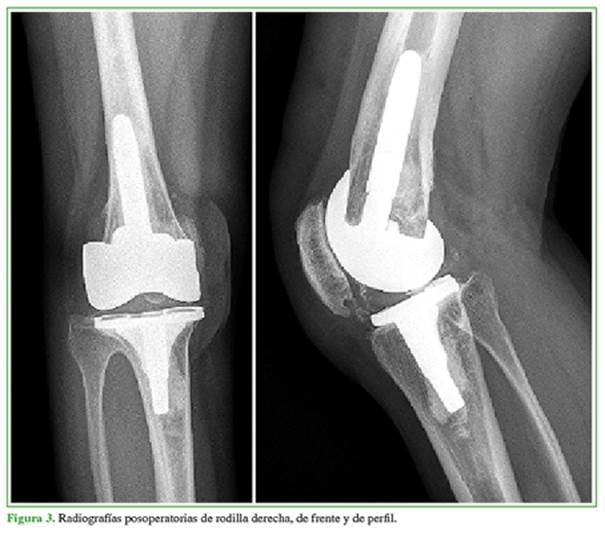

Se realizó un RTR bilateral en un solo acto quirúrgico (Figura 5). Se utilizó una prótesis estabilizada posterior con vástagos tibial y femoral para ambas rodillas. No tuvo complicaciones en el posoperatorio inmediato ni tardío. A los cuatro años de la cirugía, el rango de movilidad es de 100° y la extensión de ambas rodillas es completa. El KSS mejoró notoriamente a 87/90 en la derecha y 80/90 en la izquierda. En las radiografías, no se observan signos de aflojamiento de la prótesis (Figura 6). Refiere estar satisfecho con el procedimiento.